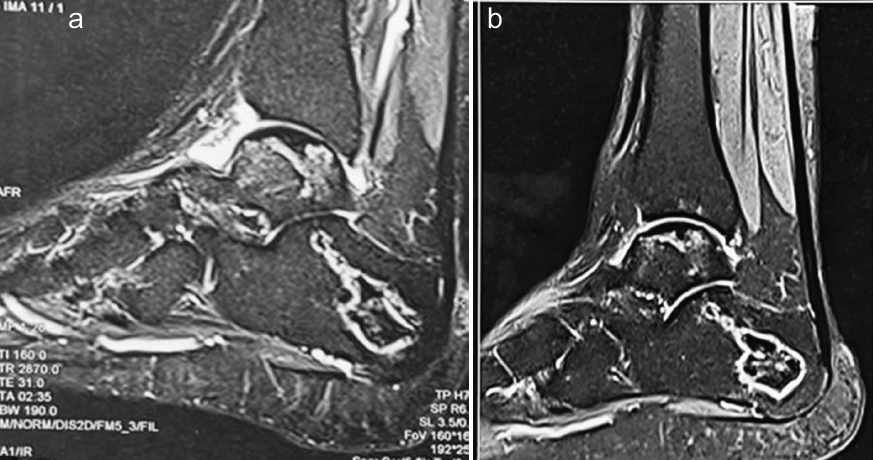

There was bilateral stage-2 involvement of the navicular, calcaneum, and talus, again with the right side being more affected than the left (Fig. 3a and b). Both knees were also classified as stage 2, with the right knee showing more severity than the left (Fig. 4a and b).

Figure 3: Pre-operative magnetic resonance imaging both ankles. 1.5 T. Proton density fat saturation sagittal images showing irregular, serpiginous hyperintensities in bilateral calcaneum, navicular, and talus (right (A) > left (B)), suggestive of bone infarcts with maintenance of contours of talar domes, calcanei, and tali.